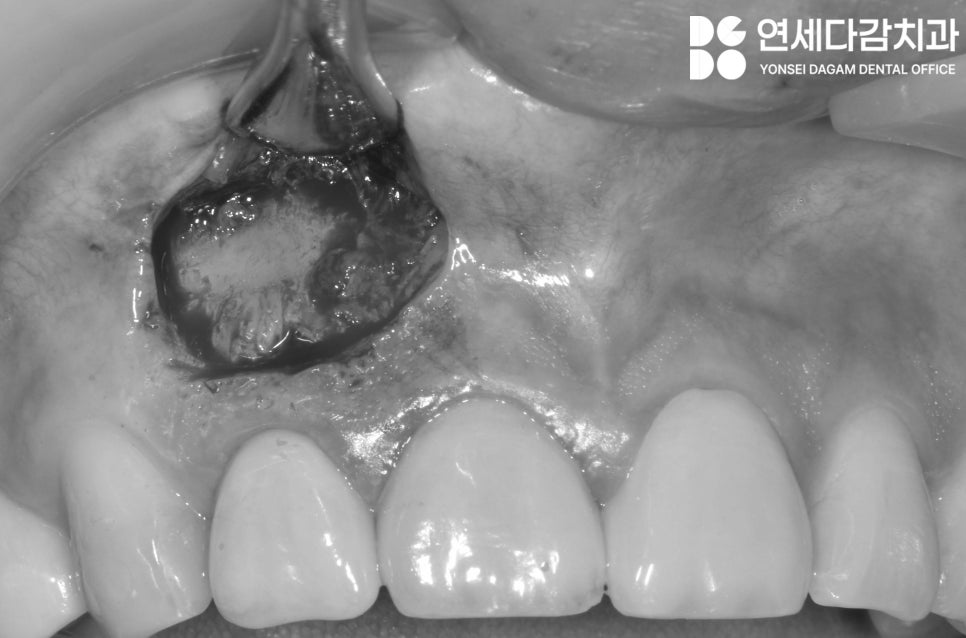

먼저 정확한 병소 위치를

파악한 후 잇몸을 절개합니다.

특히 앞니의 경우

치은 퇴축이 최소화되는 방향으로

절개선을 디자인하는 것이 중요합니다.

절개 후 치근단 병소가 있는 부위의

시야를 확보합니다.

병소 부위의 육아조직과

감염된 조직을 깨끗이 제거합니다.